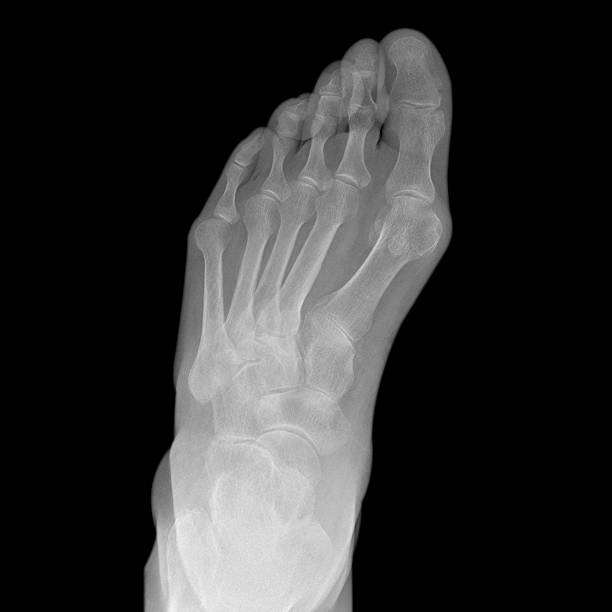

발뒤꿈치가 아픈 이유 첫 번째는 족저근막염입니다. 족저근막은 발뒤꿈치 뼈에서 시작하여 발바닥 앞쪽으로 연결되는 두껍고 강한 섬유질 띠입니다. 족저근막은 우리 몸의 중요한 역할을 하는데 아치 모양의 모양새는 우리 몸의 체중을 흡수하기 때문에 걷는 데 중요한 역할을 할 수 있습니다. 족저근막염은 이러한 족저근막에 반복되는 충격으로 근막을 둘러싸고 있는 콜라겐이 변성하면서 염증이 생긴 것을 의미합니다.

이러한 증상은 원래부터 평발이거나 걸음걸이나 생활습관 등으로 발이 변형되며 구조적으로 이상이 생겨서 문제가 생길 수도 있지만 기본적으로 하체 사용을 무리하게 하다보면 문제가 생기게 됩니다. 족저근막염 통증은 개인에 따라 다르지만 기본적으로 발뒤꿈치에 통증을 느끼게 되고 특히 아침 기상후 첫 걸음부터 통증이 나기 때문에 조기에 치료를 받는 것이 중요합니다.